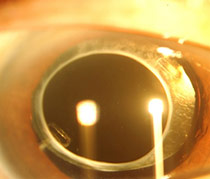

| Pearly white mature cataract caused extremely poor vision | After the removal of cataract, an intra-ocular lens is placed to restore the vision |